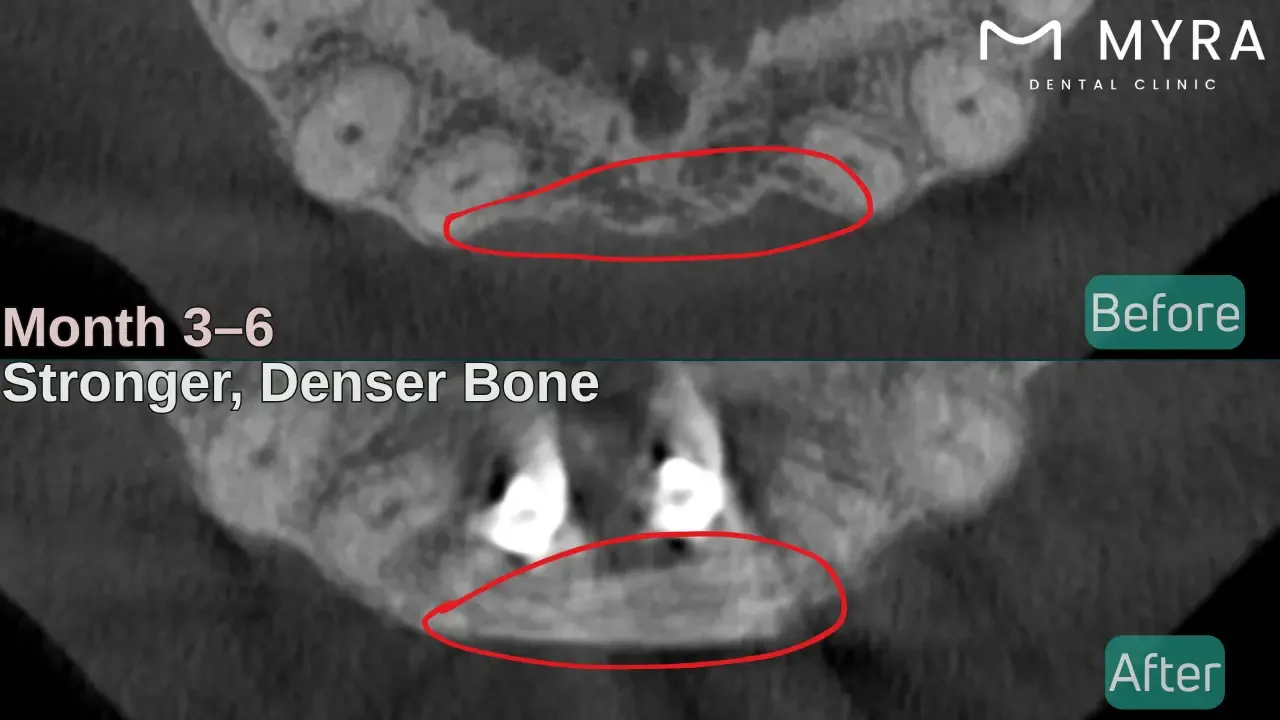

4. Bone Maturation (3-6 Months)

The bone maturation stage marks the period of mineralisation and architectural strengthening of the newly formed bone. The grafted site gradually becomes denser as immature bone is replaced with lamellar bone, which possesses higher mineral content and organised collagen fibres.

Osteoclasts contribute by removing non-viable graft particles, allowing space for mature tissue to occupy the site. The bone begins to behave like native bone, providing sufficient support for upcoming dental procedures, such as implant placement.

The affected area gains resistance against physical forces and better vascular integration, preparing for permanent prosthetic restoration.